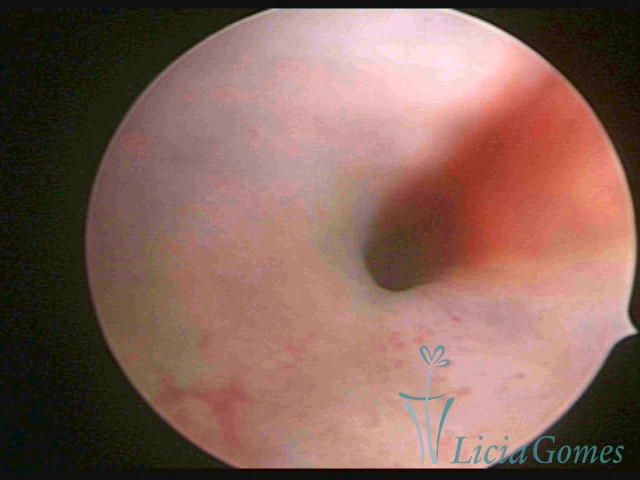

Third part or upper section

Presents the mucosa with a smooth, poorly vascularized surface, to the internal orifice